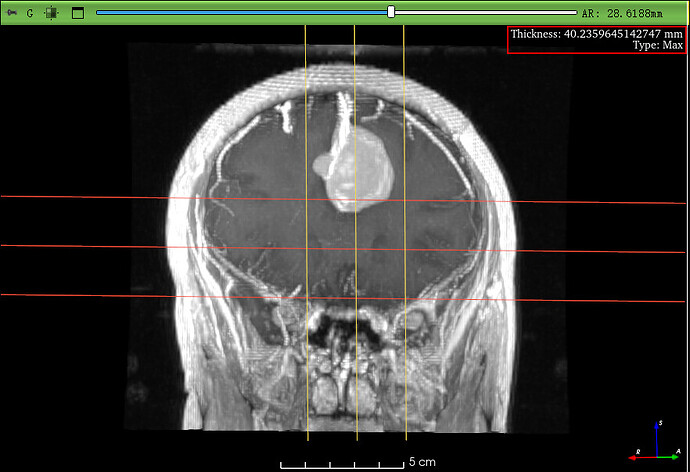

GIF 动图展示了在 1 mm 厚度下开启 MIP 后,脑膜瘤强化区的信号更加明亮清晰。

| 增强MRI 病灶观察 | Type: MIP Thickness: 5–8 mm | 强化病灶信号,边界更清晰 |